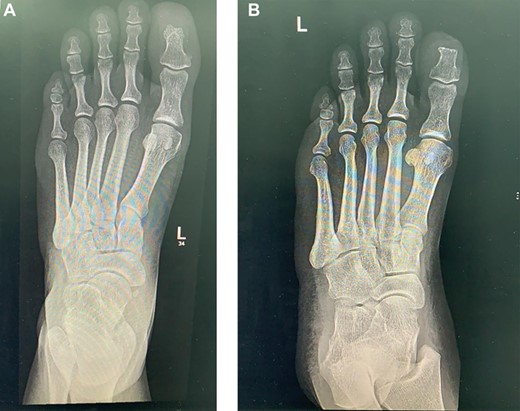

The laboratory data included a white blood cell count of 6000/μl, hemoglobin of 10.5 g/dl, platelet count of 233 × 10/μl, blood glucose 121 mg/dl, blood urine nitrogen 46 mg/dl, serum creatinine 69 mg/dl, sodium 138 mmol/L, potassium 3.8 mmol/L, serum albumin 3.4 g/dl, erythrocyte sedimentation rate 73 mm/h, and C-reactive protein 15.6 mg/dl. The X-ray of lower extremity revealed no significant abnormality (Fig. 1).

Left foot X-ray 19 months post excision and coverage with Kutler bilateral V-Y advancement flaps no evidence of recurrence.